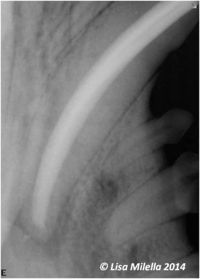

Root canal therapy 1

Root canal therapy 2

Root canal therapy 3

Root canal therapy 4

The objectives of conventional root canal therapy are: (pic30-33)

• To clean and disinfect the pulp chamber and root canal(s).

• To fill the root canal(s) with a nonirritant, antibacterial material, thus sealing the apex.

• To close the access and exposure sites with a suitable restorative material.

The whole procedure is performed under general anesthesia and under strict radiographic control. It is time-consuming, as each step needs to be performed with meticulous detail to ensure a successful outcome. The outcome of conventional root canal therapy should be monitored radiographically for 6–12 months postoperatively, then ideally every year thereafter.